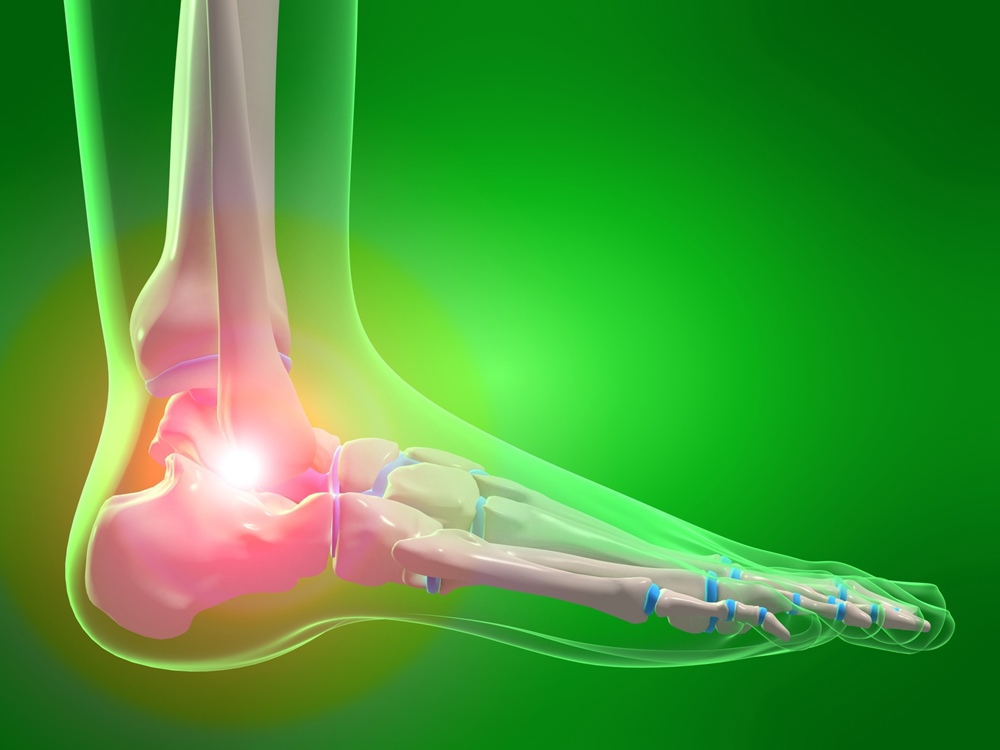

Медицинские состояния: Септический артрит коленного сустава